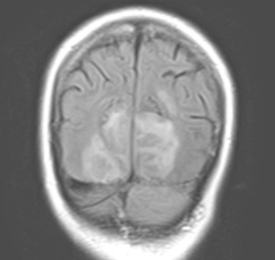

Описание клинического случая. Пациентка 63 лет с хронической артериальной гипертензией 3 ст., 3 ст., риск 4 и сахарным диабетом 2 типа планово поступила для хирургического вмешательства по поводу рака прямой кишки. Во время операции под общей анестезией у пациентки отмечалась нестабильная гемодинамика с повышением АД максимально до 160\100 мм.рт.ст.. После пробуждения пациентка отметила отсутствие зрения и нарушение координации, всё это сопровождалось неконтролируемой артериальной гипертензией с подъёмом АД максимально до 182\130 мм.рт.ст.. На МРТ в обеих затылочных долях (справа 43 мм х 26,5 мм х 40 мм) отмечались участки гиперинтенсивного сигнала в режиме Т2 без признаков ограничения диффузии, паравенктрикулярно в белом веществе головного мозга - очаги до 2 мм сосудистого генеза. Неврологические нарушения пациентке удалось купировать, зрение восстановилось в течение 2 недель.